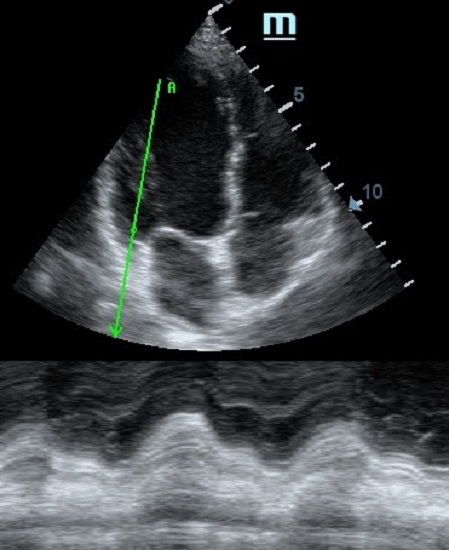

TAPSE - показатель амплитуды движения латеральной части кольца трикуспидального клапана, позволяет количественно и быстро оценить систолическую функцию правого желудочка, норма которого составляет более 17 мм. Главным условием является проведение линии М-режима параллельно стенке правого желудочка в апикальном четырех камерном сечении, что легко достигается при Free Xros.

MAPSE - амплитуда движения латерального кольца митрального клапана, позволяет рассчитать фракцию выброса по формуле EF = 4.8 × MAPSE (mm) + 5.8, очень быстрый и гораздо более точный («прародитель Strain») метод чем широко распространенный метод Teicholtz. В современных приборах можно легко добавить свою формулу при отсутствии ее в стандартном калькуляторе. Главным условием является проведение линии М-режима параллельно стенке левого желудочка в апикальном четырехкамерном сечении, что легко достигается при использовании функции Free Xros.